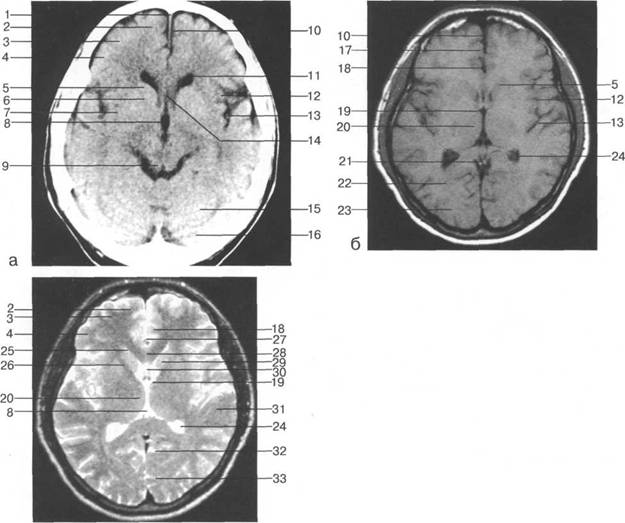

мие; 26 - поясная борозда; 27 - головка хвостатого ядра; 28 - бледный шар; 29 - височный рог боково

В латеральных отделах дно передней череп 13513u2010n 85;ой ямки образовано крышами глазниц, а в центральном - продырявленной пластинкой. Базальные отделы лобных долей представлены ко

ные извилины (рис. 1.10). Структуры средней череп 13513u2010n 85;ой ямки ограничены спереди малым крылом основной кости, снизу - большим крылом, сзади - передней поверхностью пирами «edge» «bone»

Содержимое средней череп 13513u2010n 85;ой ямки представлено базальными отделами височной доли.

цистерна четверохолмия; 14 -прямой синус; 15 -лобный рог; 16 - головка хвостатого ядра; 17 -перед

III ди зрительного бугра идет ретроталамическая цистерна, ориентированная во фронтальной